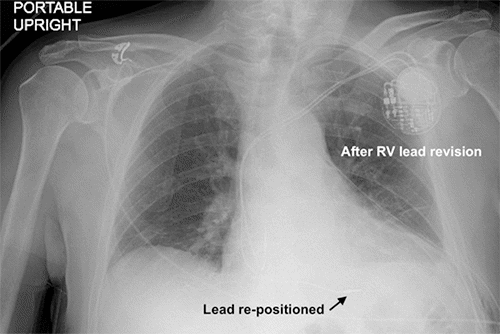

The patient went home and was doing well for the next several days. He wears a standard CPAP mask at night and has been doing so for several years. On the morning of postoperative day 5, he woke up with severe shortness of breath. He returned to the emergency department. In the ED, his vitals were normal, and he maintained oxygen saturation above 90% on nasal cannula. CXR demonstrated a large left pneumothorax with a left-to-right mediastinal shift (Figure 2). The surgery team was consulted at this time and placed a 20 Fr chest tube into the left chest with an evacuation of a significant amount of air. Even though he had a mediastinal shift, he had not yet developed tension physiology. Postprocedure CXR demonstrated resolution of the PTX, but the ventricular pacemaker lead appeared out of place (Figure 3). With no history of chronic obstructive lung disease or prior imaging suggestive of blebs, we concluded that this PTX was most likely a technical complication of our left subclavian vein cannulation.

Figure 2. Left Pneumothorax (PTX) on Postoperative Day 5. Published with Permission

Appearance after five nights of continuous positive airway pressure (CPAP) therapy. Note left-to-right mediastinal shift; still, patient had normal vitals.